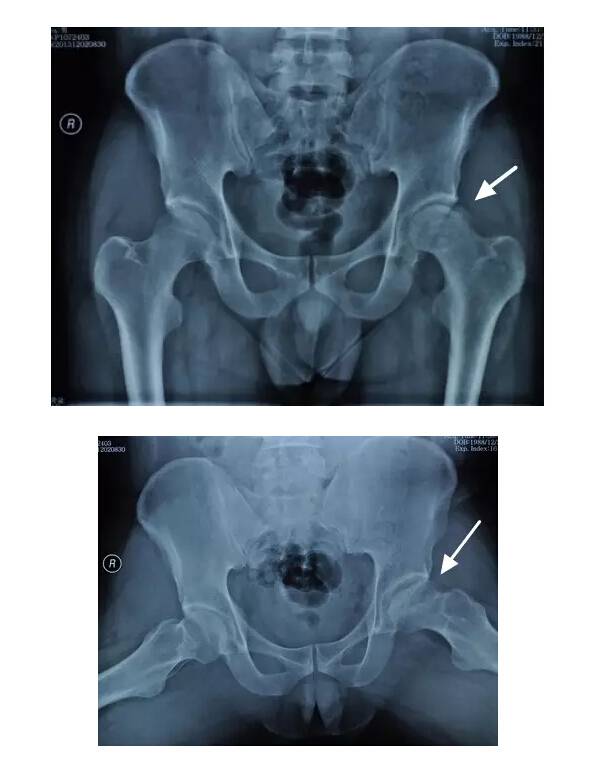

II期病人有髋部症状,磁共振出现异常,X线片显示股骨头出现透光和硬化改变

III期磁共振出现异常,X线片显示软骨下塌陷(新月征),股骨头内出现空洞,股骨头没有变扁